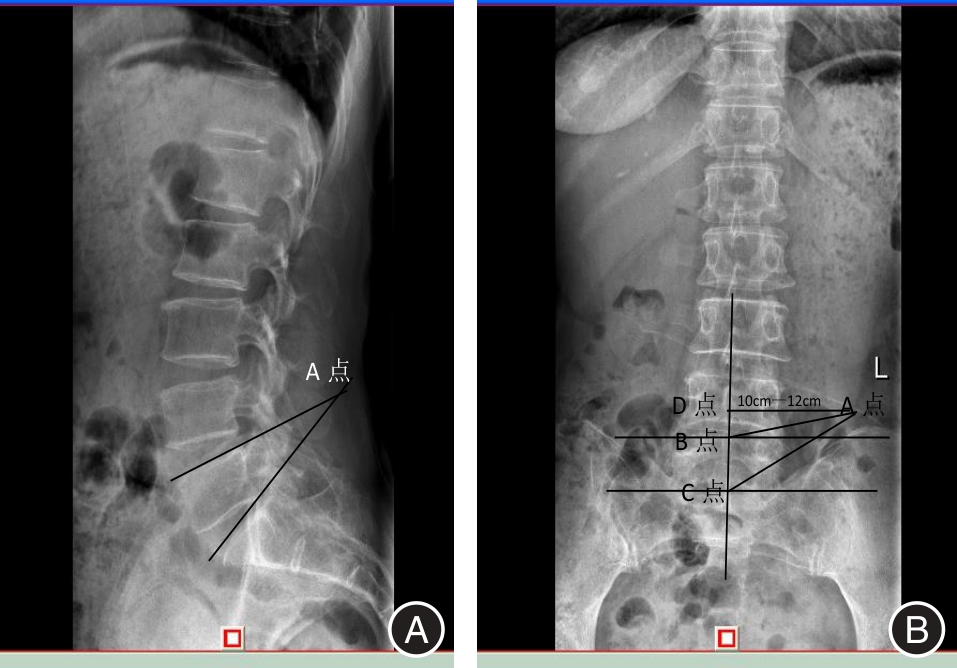

目的 探讨单一切口椎间孔镜治疗双节段腰椎管狭窄并腰椎间盘突出症的临床疗效。 方法 回顾性分析2016年3月至2018年5月在广西中医药大学第一附属医院脊柱骨伤科就诊的40例双节段腰椎管狭窄并腰椎间盘突出症患者临床资料,其中通过单一切口同时穿刺椎间孔镜治疗的患者11例(A组),通过单一切口前后穿刺椎间孔镜治疗的患者13例(B组),通过双切口前后穿刺椎间孔镜治疗的患者16例(C组)。记录患者的一般临床资料,三组不同时间点(术前、术后即刻、术后1周、术后1个月、末期随访)的VAS评分、JOA评分及临床疗效,并运用统计学进行分析。 结果 三组间手术时间、术中透视次数、皮肤切开长度和满意度差异均有统计学意义(P < 0.05);手术时间与手术方式在VAS、JOA评分上存在交互作用;手术时间、手术方式在VAS、JOA评分上存在主效应(P < 0.05);三组术后即刻、术后1周、术后1个月、末期随访与术前在VAS、JOA评分上比较差异均有统计学意义(P < 0.05);三组间术后即刻在VAS、JOA评分上差异有统计学意义(P < 0.05);三组间术后1周在VAS评分上差异有统计意义(P < 0.05)。 结论 单一切口椎间孔镜技术同时减压双节段腰椎管狭窄并腰椎间盘突出症的有效手段,具有手术时间短、术中透视少,损伤小等优势,患者满意,值得临床推广应用。

Objective To evaluate the clinical effectiveness of single?incision intervertebral foraminotomy in treating double?segment lumbar spinal stenosis accompanied by lumbar disc herniation. Methods A retrospective analysis was conducted on 40 cases of double?segment lumbar spinal stenosis and lumbar disc herniation treated in our orthopedic (spinal surgery) department from March 2016 to May 2018. Among these cases, 11 patients (Group A) were treated with percutaneous discectomy, 13 patients (Group B) underwent percutaneous endoscopic discectomy, and 16 patients (Group C) received double?incision percutaneous surgery. General clinical data for all patients were recorded. Visual Analog Scale (VAS) scores, Japanese Orthopaedic Association (JOA) scores, and clinical outcomes were assessed at five different time points: preoperatively, immediately postoperatively, one week postoperatively, one month postoperatively, and at the final follow?up. Statistical analysis was performed on the collected data. Results The operation time, the number of fluoroscopies performed on the hands, the length of the skin incision, and patient satisfaction were all statistically significant (P < 0.05). An interaction effect was observed between the operation time and the surgical procedure on both the VAS and JOA scores. Both the operation time and the surgical method had significant main effects on the VAS and JOA scores (P < 0.05). Significant differences in VAS and JOA scores were found among the three groups immediately post?surgery, one week post?surgery, one month post?operation, and at the end of the study (P < 0.05). Immediately after surgery, there were statistically significant differences in VAS and JOA scores among the three groups (P < 0.05). One week post?surgery, there were also statistically significant differences in VAS scores among the three groups (P < 0.05). Conclusions The single?incision intervertebral foramen technique is an effective approach for simultaneously addressing double?segment lumbar spinal stenosis and lumbar disc herniation through decompression. This method boasts a shorter operative duration, reduced intraoperative radiation exposure, and minimal tissue damage. Patient satisfaction is high, making it a valuable addition to clinical practice.